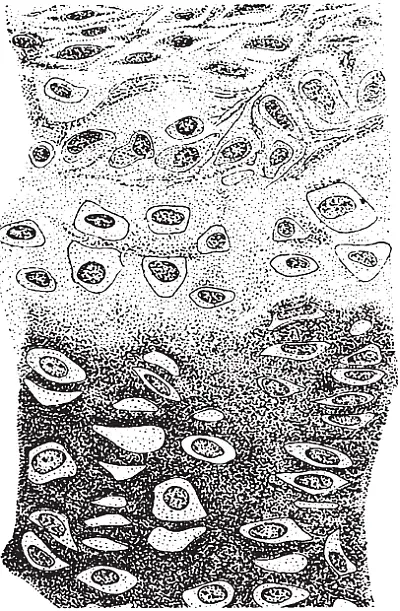

Сама хрящевая ткань выполняет опорную функцию и отличается упругостью. Она состоит из хрящевых клеток и основного вещества.

Хрящ кажется сплошным и гладким. На самом деле он составлен из плотно уложенных пучков коллагеновых волокон. Также в основном веществе хрящей имеются хрящевые клетки.

Значение воды для хряща огромно. Хрящ содержит гораздо больше воды, чем кость. Напоенный водой хрящ здоров, крепок и гладок. Он прекрасно выдерживает нагрузки и скользит по смежной поверхности. В хряще должно поддерживаться определенное давление воды, которое при нагрузке увеличивается. Особенно это касается межпозвоночных дисковых соединений. В наибольшей степени – в поясничном отделе позвоночника.

Если в хрящах мало воды и/или нагрузка недостаточная или чрезмерная, то возникает значительное трение, сухость и отшелушивание клеток. Соотношение между нарастанием клеток и отшелушиванием служит показателем состояния сустава.